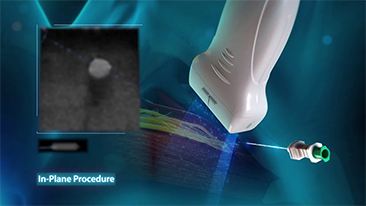

Bij focale leverlaesies, zoals hemangioom of leverkanker, speelt ultrasone contrastbeeldvorming een belangrijke rol. Ultrabrede niet-lineaire UWN+ contrastbeeldvormingstechnologie kan helpen bij het verkrijgen van een betere penetratie, een hogere contrast-weefselverhouding, met een lagere MI en een langere observatie van de perfusietijd.